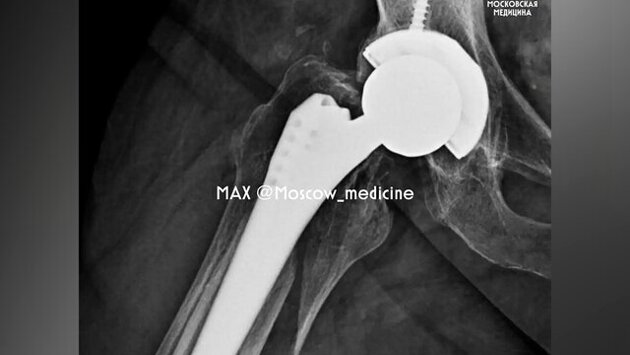

По данным ведомства, 66-летняя жительница Москвы торопилась на работу, однако упала и получила перелом бедренной кости. Травма была зафиксирована в том месте, где в 2018 году женщине установили эндопротез.

Во время операции хирурги удалили нестабильные фрагменты, собрали костные отломки с помощью серкляжной системы и установили новый эндопротез. Спустя шесть дней женщину выписали домой на реабилитацию.